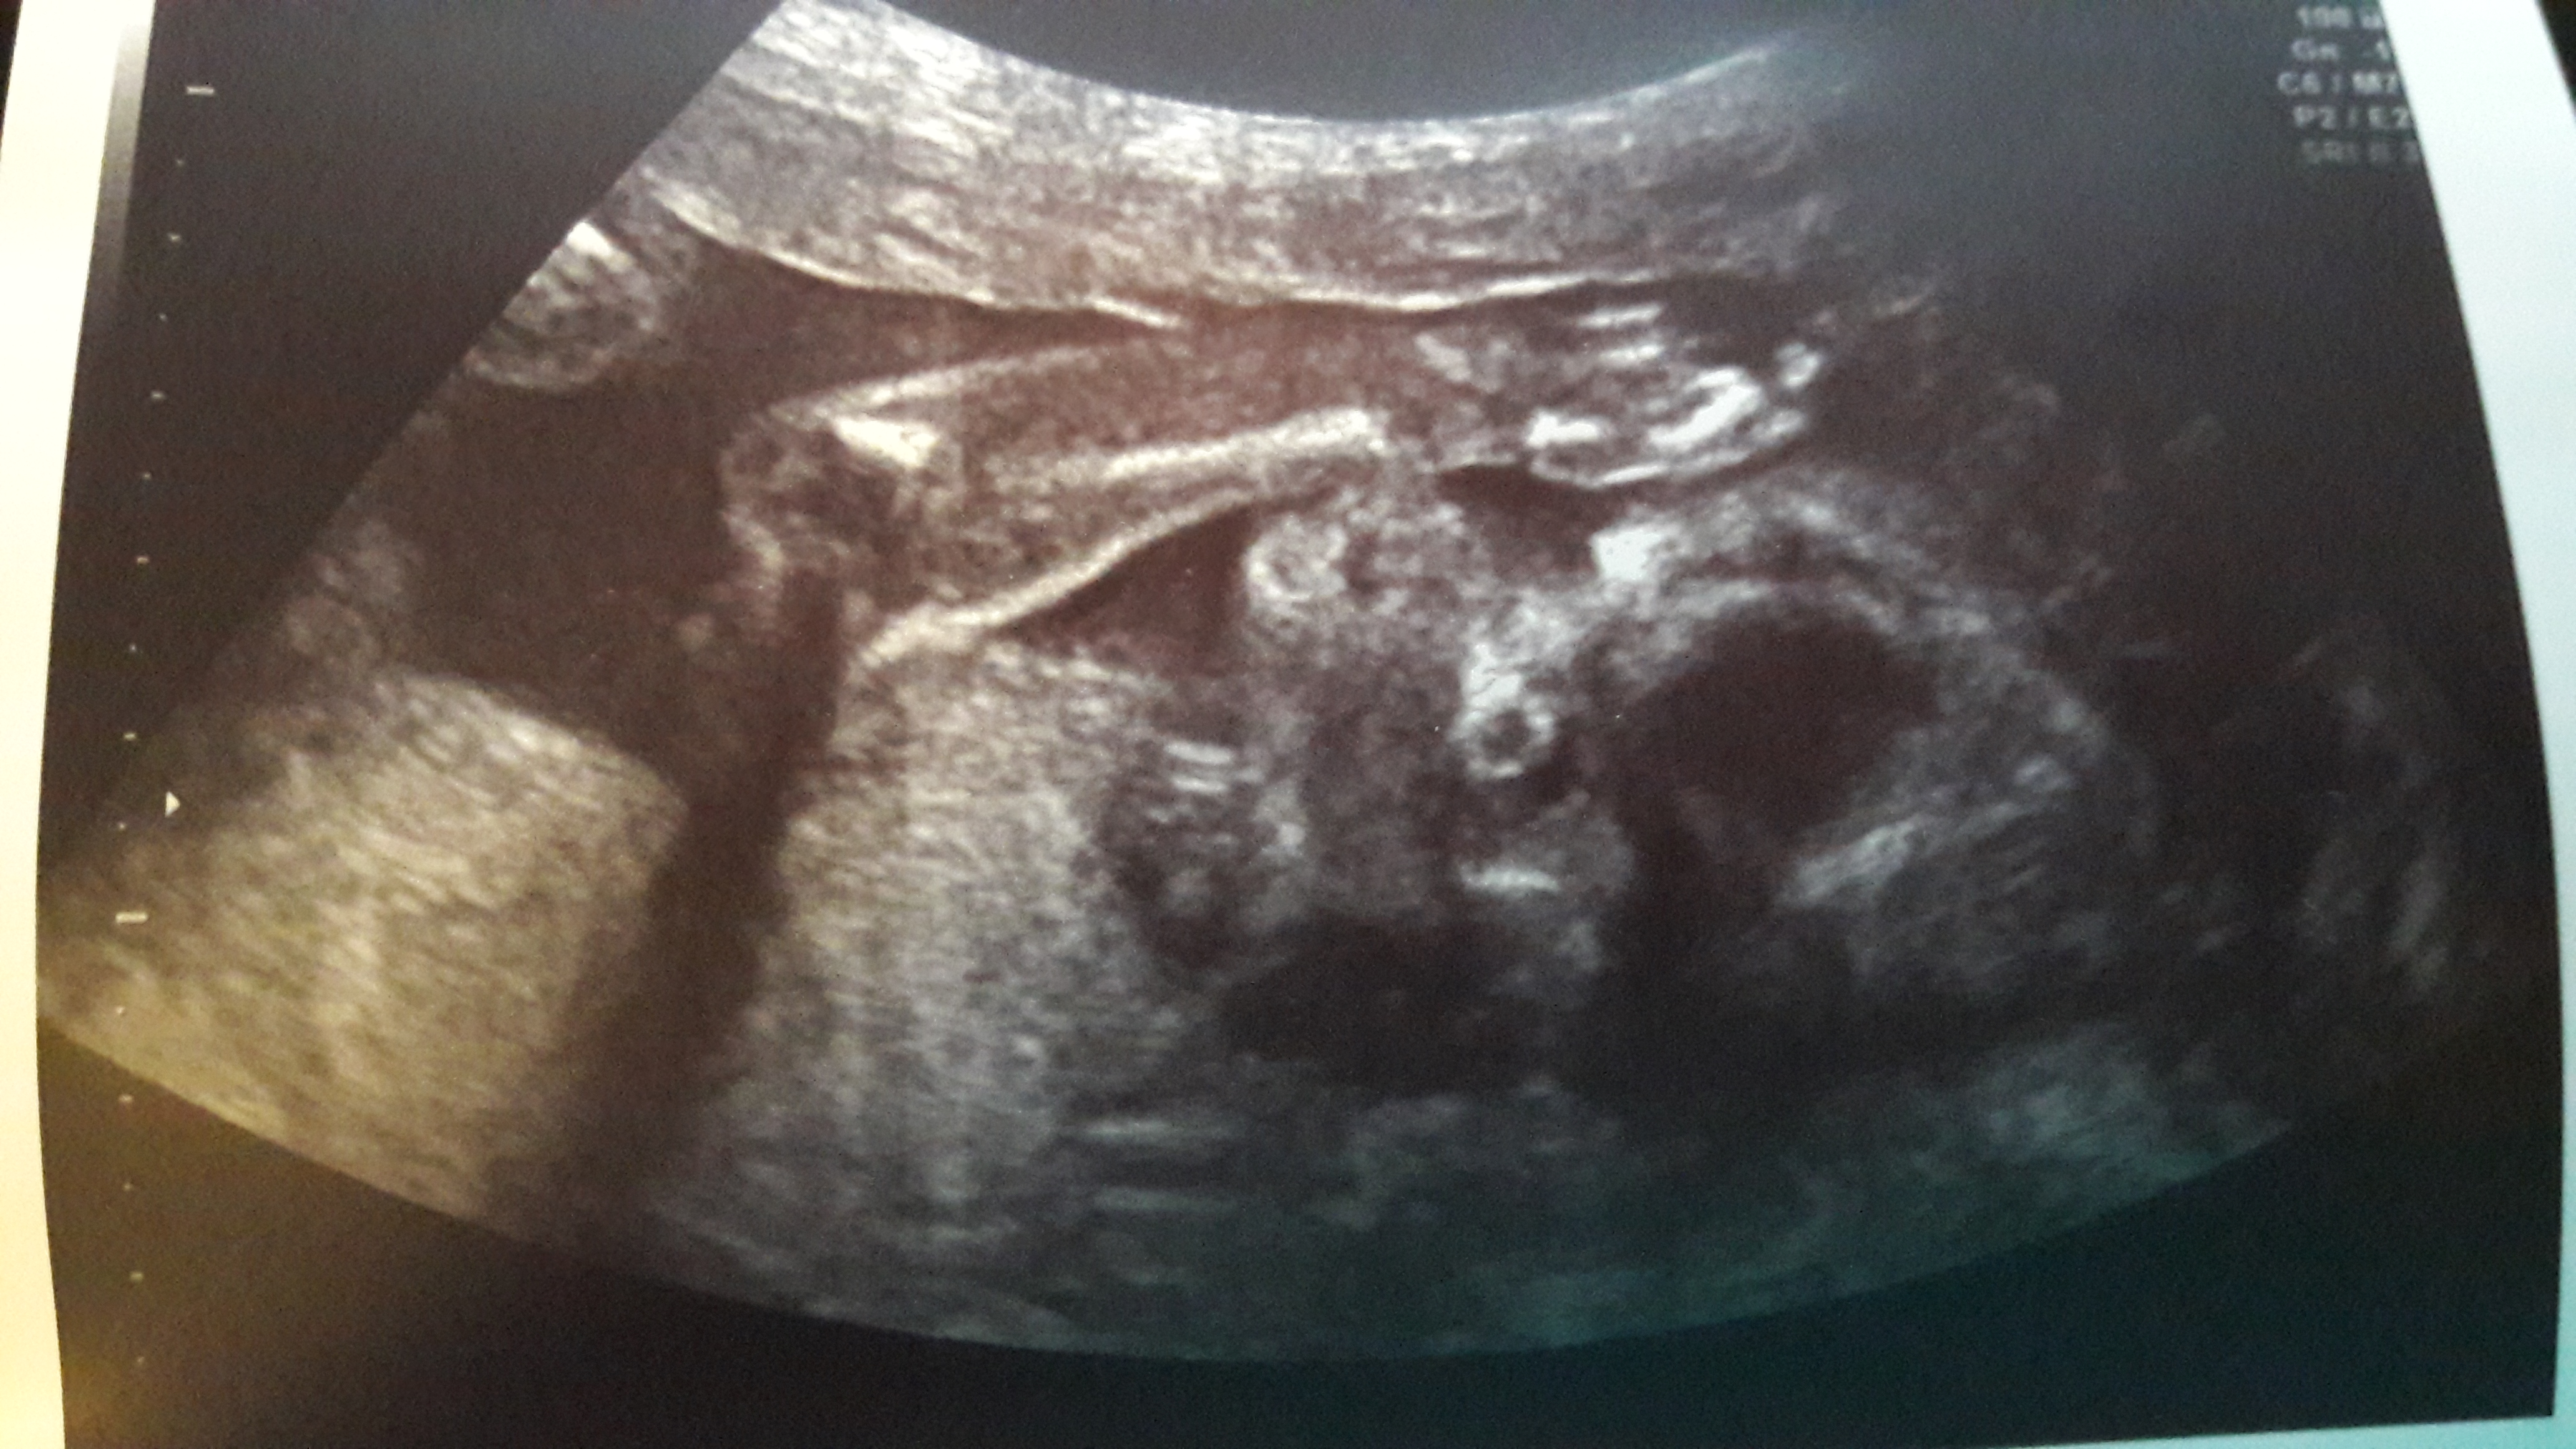

Hoi iedereen! Wat leuk dat je er weer bent! Zoals beloofd zou ik een post schrijven over de nieuwe zwangerschap, dus lees lekker verder. Laat ik beginnen met de manier waarop we het ontdekten. Ik was nog steeds niet ongesteld omdat onze miniman nog borstvoeding krijgt, dus uitblijven van menstruatie was geen teken waar ik … Meer lezen over Zwanger!? Hoezo? | Mama met Sokjes van Geitenwol